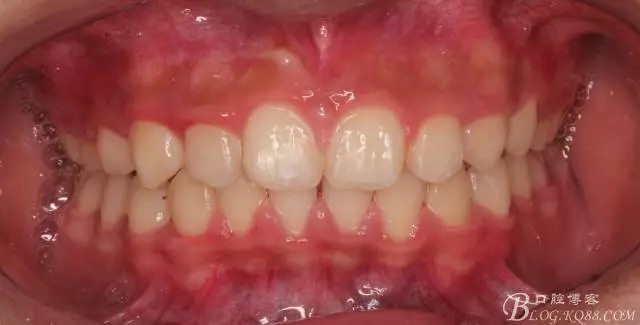

看看口內(nèi)照吧!真象“大暴牙”v假象“大暴牙”

三度深覆合,三度深覆蓋,尖牙,磨牙均二類關(guān)系!

640.webp (1).jpg